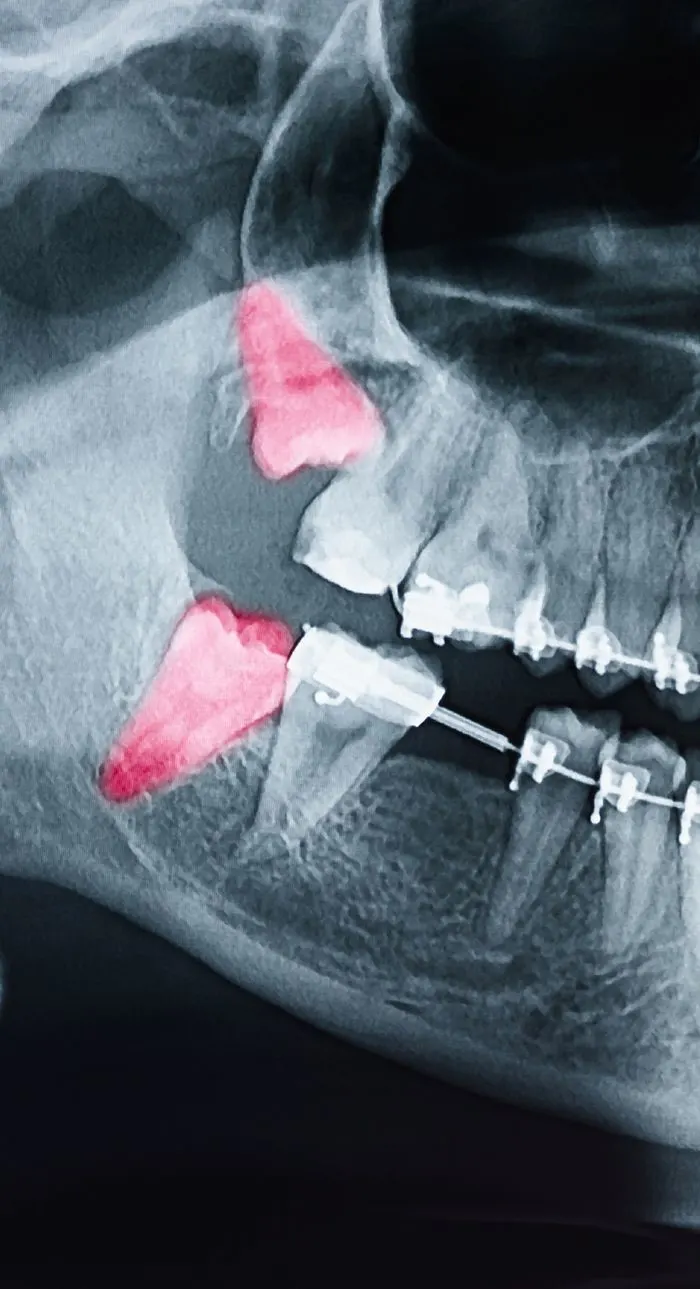

With digital x-rays, we get high-resolution images of your teeth that allow us to make more accurate diagnoses. When you’re in pain or experiencing an emergency, we can see why the tooth is reacting and if an extraction is needed.

The most common reason for tooth extractions is improper wisdom teeth growth. If your dentist determines that your wisdom teeth are impacted or not erupting correctly, extraction may be recommended to protect the health of your other teeth. Not everyone requires wisdom teeth removal, so it’s important to consult your dentist to determine if yours pose a problem.